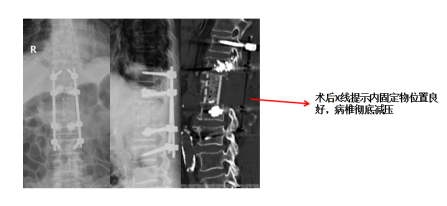

住院后,在麻醉团队配合下,由南京江北医院副院长、骨科中心李涛主任主刀,带领脊柱外科团队耐心细致地将患者腰1椎体病损顺利切除。